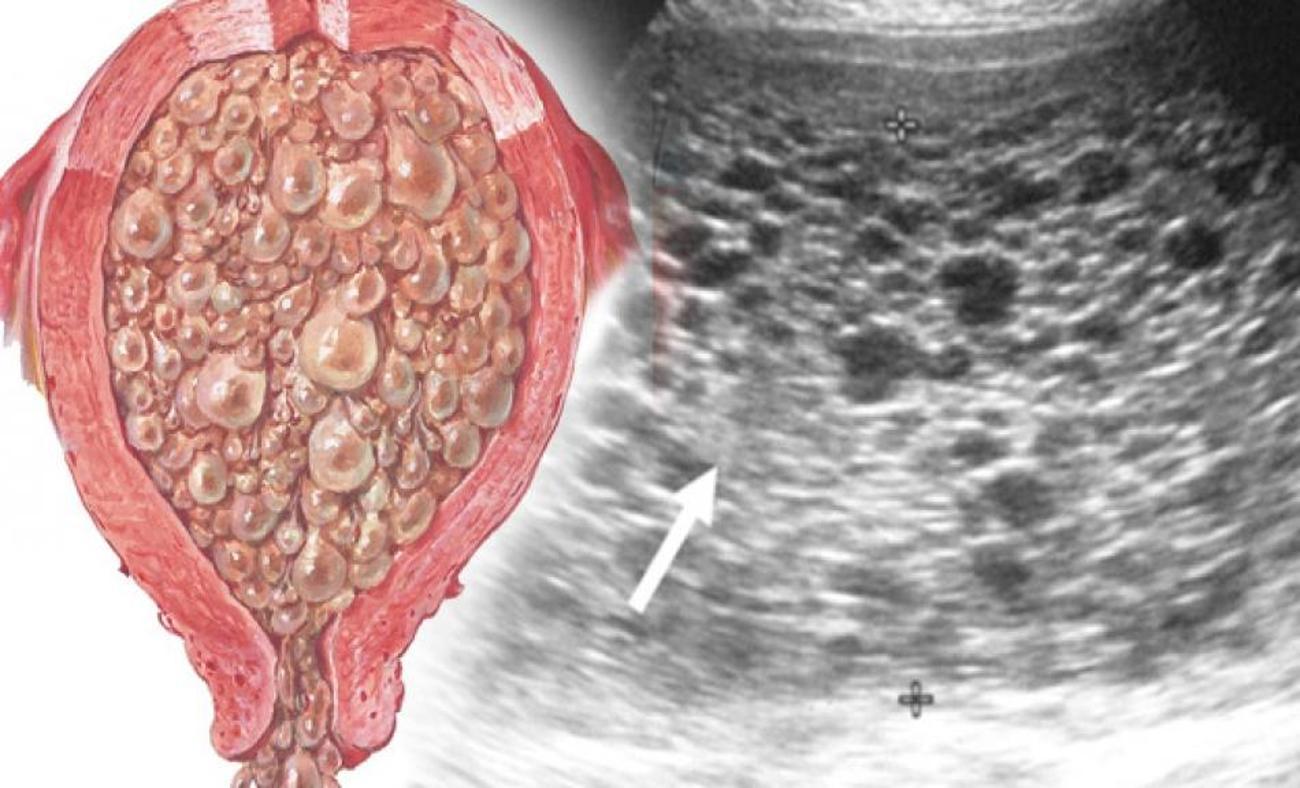

Медицина и диагностика: Инвазивный пузырный занос на УЗИ

Раздел: Альбом идей